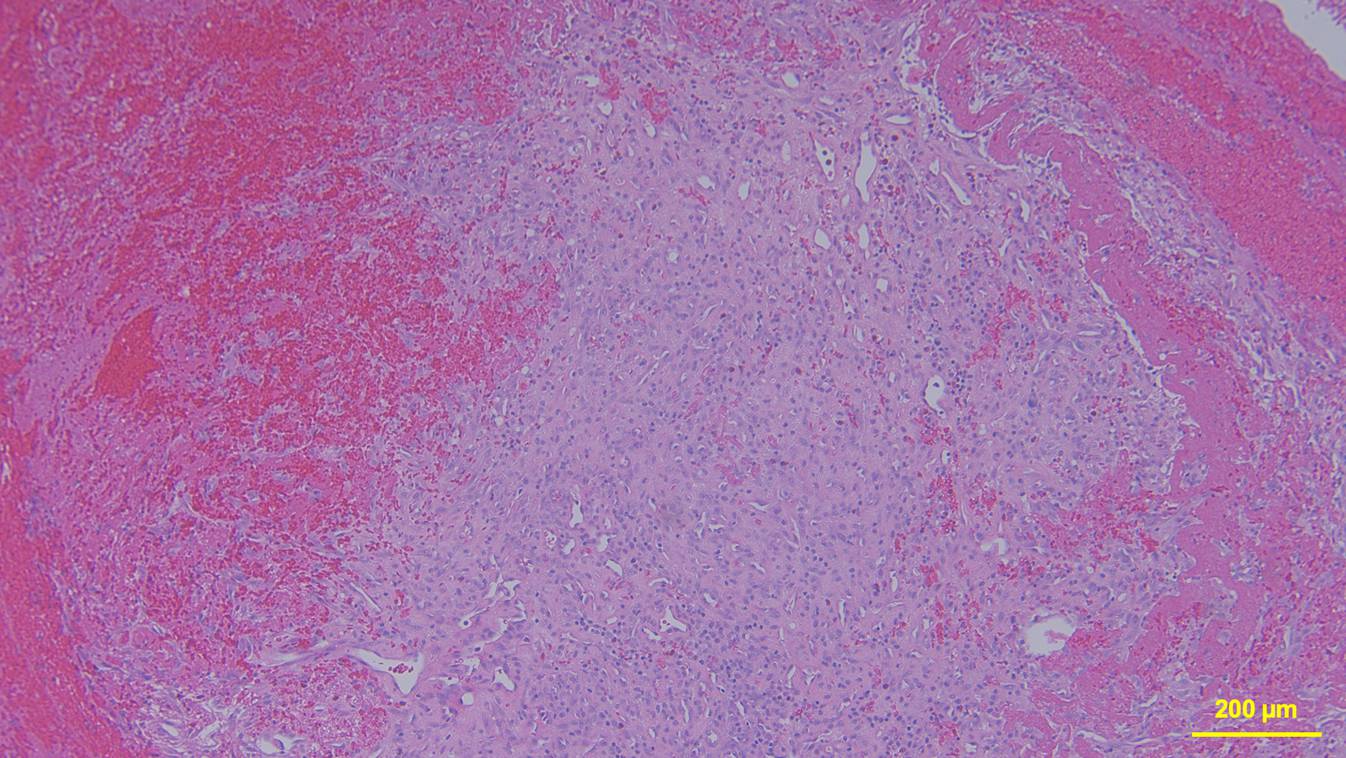

Die histopathologische Aufarbeitung ergab: Fibröses Bindegewebe mit einliegender, leicht atropher Skelettmuskulatur. Daneben flächige Erythrozytenansammlungen durchsetzt mit Fibrin und korpuskulären Blutbestandteilen. Angrenzend knotiges Granulationsgewebe mit Kapillar- und Fibroblastenproliferaten sowie Histiozyten (Abb. 6). Kein wesentlicher florider inflammatorischer Prozess. Keine atypischen Zellinfiltrate. In der histologischen Gesamtbeurteilung ergibt sich eine atrophe Skelettmuskulatur mit älteren Einblutungen und einer assoziierten chronisch-resorptiven Entzündungsreaktion.

Abb. 6

Exemplarischer mikroskopischer Befund der exstirpierten Raumforderung. HE-Färbung

Histopathologisch ist dieser Befund mit einer chronisch-entzündlichen Reaktion auf einen Fremdkörper zu vereinbaren. Bei fehlendem Fremdkörpernachweis ist am ehesten von einer vollständigen Resorption auszugehen.